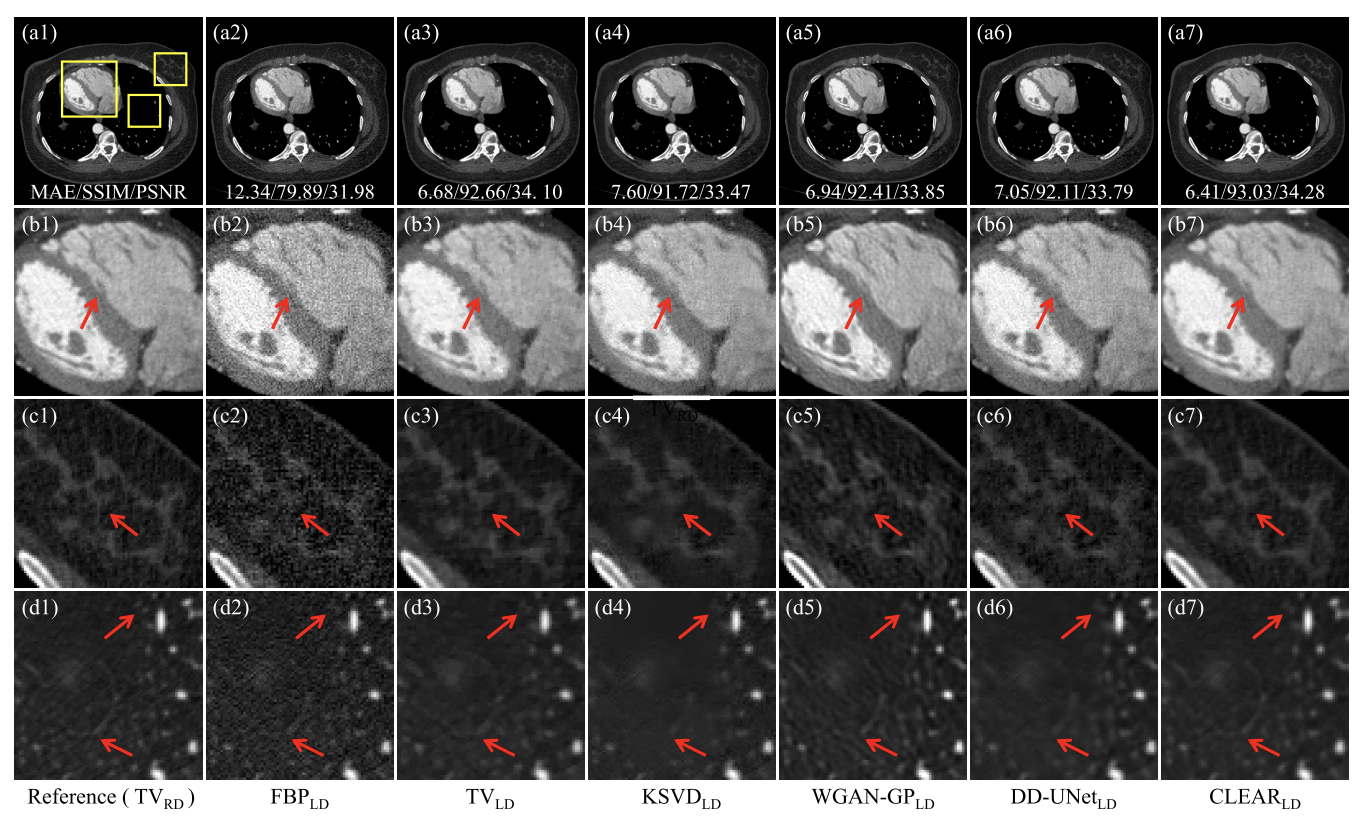

- 실제 데이터

- FBP: 노이즈는 이미지의 미세한 특징을 심각하게 손상

- TV: 블록 artifact 발생( c3)

- KSVD: 흐림효과, 미세한 구조 손실(d4)

- DD-UNet:노이즈 억제 x, 세부사항 보존 x

- WGAN-GP , CLEAR: 좋은 시각적 인식(CLEAR가 구조적 충실도에서 더 유망한 성능)

정량적 평가

- CLEAR: 가장 높은 SSIM과 PSNR,가장 낮은 MAE

- TV>WGAN-GP, DD-UNet: 데이터 기반 방법-> 실제 프로젝션과 시뮬레이션된 프로젝션 간의 불일치